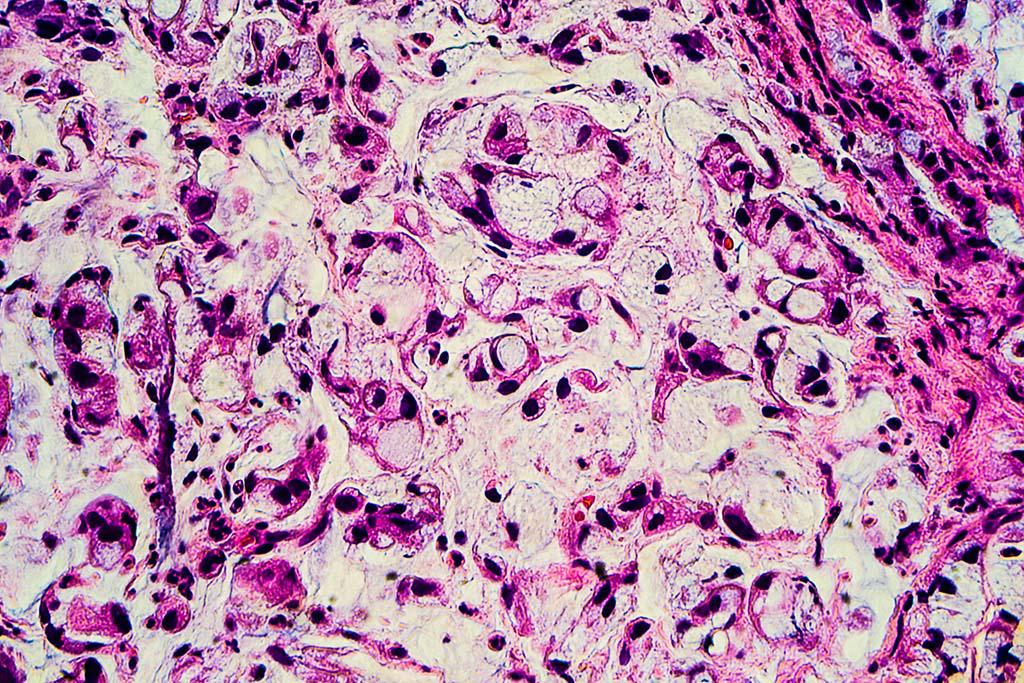

Çocuklarda en sık görülen kanser türlerinden biri olan “akut limfoblastik lösemi”ye, mikroplardan arındırılmış yaşam biçiminin yani “fazla hijyenik” koşulların neden olduğu ileri sürüldü. Bu tezin sahibi İngiltere’nin önde gelen kanser uzmanlarından Profesör Mel Greaves.

İngiltere’nin önde gelen kanser uzmanlarından biri olan Profesör Mel Greaves, mikroplardan arındırılmış modern yaşam biçimimizin çocuklarda en sık görülen kanser türlerinden birine yol açtığını söyledi.

BBC Türkçe’de yer alan James Gallagher imzalı habere göre, Akut Limfoblastik Lösemi her iki bin çocuktan birini etkiliyor. Kanser Araştırmaları Enstitüsü’nden Profesör Greaves, 30 yıldır yapılan araştırmalarda görülen kanıtların, yaşamın ilk yıllarında yeterli derecede mikroba maruz kalmazsa, bağışıklık sisteminin kanserojen olabileceğini gösterdiğini söyledi.